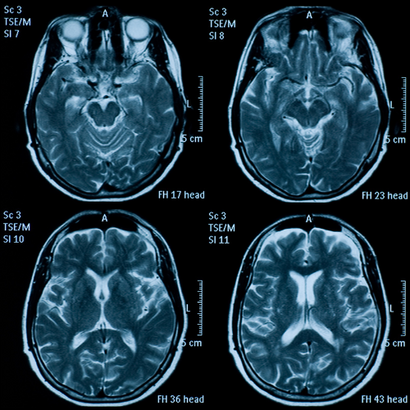

Los sujetos se sometieron a una resonancia magnética craneal, al principio y dos años después del tratamiento. Estos análisis, junto con los análisis del plasma, mostraron que en los sujetos con concentraciones elevadas de ácidos grasos, el tratamiento con vitaminas había ralentizado la tasa de crecimiento de la atrofia en un 40,0% en comparación con el placebo.